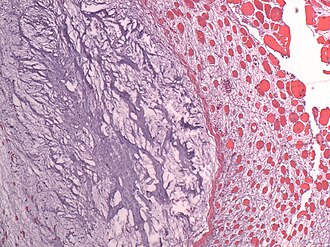

LM myxoid stroma with bland stellate cells and/or bland spindle cells, intramuscular, usu. hypervascular and hypercellular

Microscopic

Features:[1][3]

• Myxoid stroma - key feature

• Bland stellate or spindle cells.

• Typically paucicellular. †

• Usually with scant vascularity. ‡

• Contained within skeletal muscle - essential.

Note:

• † A hypercellular variant exists.

• ‡ A hypervascular variant exists.